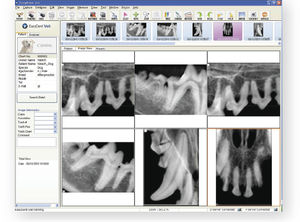

software de visualización DICOMEasyDent

... El software fácil de usar de Rayence permite adquirir, gestionar y procesar imágenes digitales de diagnóstico y el software complementa las imágenes de alta calidad con una velocidad excepcional. Su transmisión en tiempo ...